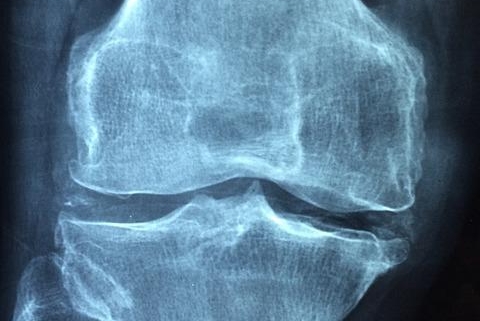

Osteoarthritis: This is the most common form of arthritis. It occurs when the protective cartilage that cushions the ends of your bones wears down over time.